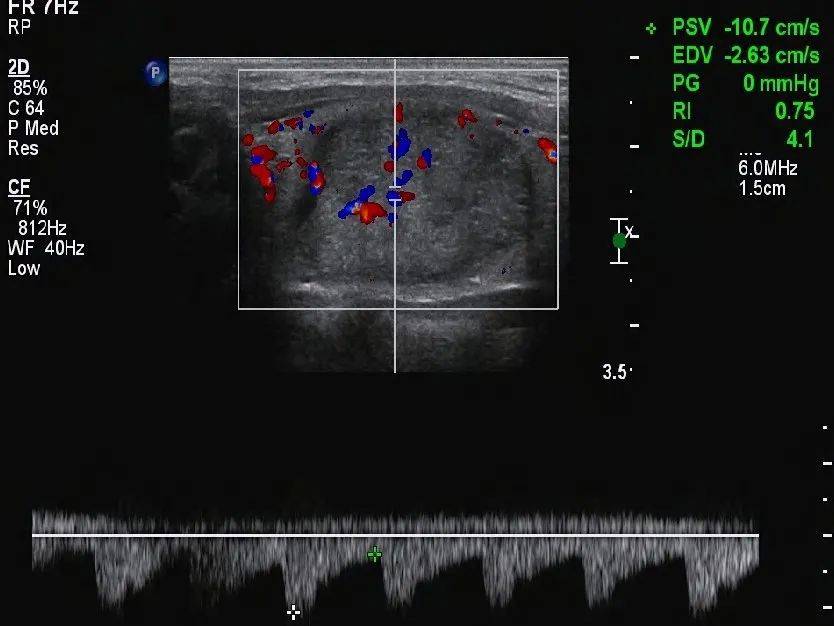

甲状腺形态失常,左侧叶增大,内部回声不均匀,见囊实混合性结节,大小约 33mm×19mm×28mm ,形态规则,边界清,纵横比 <1 ,内部以实性为主,实性部分见少许散在点状强回声(图 1 、图 2 ),结节周边伴低回声声晕,声晕厚度不均匀(图 3 ), CDFI:结节周边见环绕血流信号,内部见不规则分布的血流信号,局部较丰富(图 4 、图 5 )。SMI:结节局部微细血流信号丰富(图 6 )。

图 4 CDFI 示内部可见血流信号

图 5 血流频谱